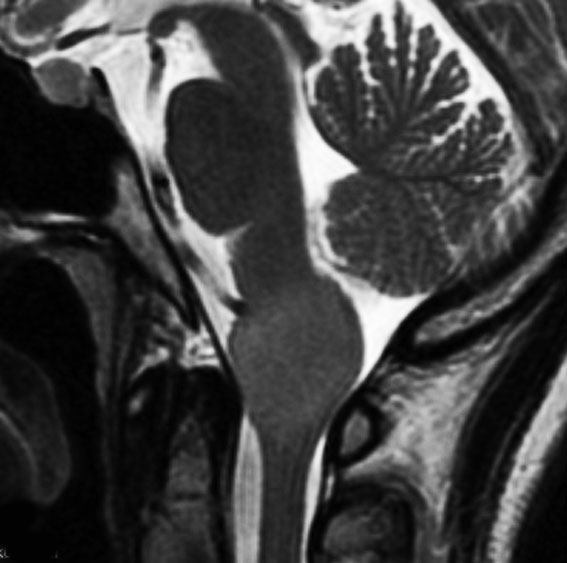

20代の若い患者さんの延髄下端のdiffuse midline gliomaです,組織診断ではanaplastic astrocytomaでした